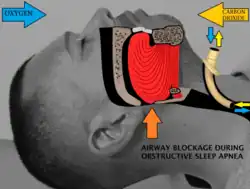

Sleep surgery is a range of surgical procedures to treat sleep-related breathing disorders (sleep-disordered breathing), especially obstructive sleep apnea (OSA). The spectrum of sleep-related breathing disorders also includes primary snoring (non apneic snoring), upper airway resistance syndrome, and obesity hypoventilation syndrome. These surgeries are performed by surgeons trained in otolaryngology, oral maxillofacial surgery, and craniofacial surgery.

Obstructive sleep apnea (OSA) is defined as either cessation of breathing (apnea) for 10 seconds, or a decrease in normal breathing (hypopnea) with an associated desaturation in oxygen and arousal during sleep that lasts at least 10 seconds. In adults, it is typical to have up to 4.9 events per hour. In OSA, affected individuals are categorized based on how many apneas or hypopneas (apnea-hypopnea index or AHI) or events they have per hour.

Sleep surgery aims to reduce daytime sleepiness, increase quality of life, and improve parameters recorded on polysomnography.[2] In general, all the procedures achieve this by removing or preventing obstruction of the upper airway during sleep.